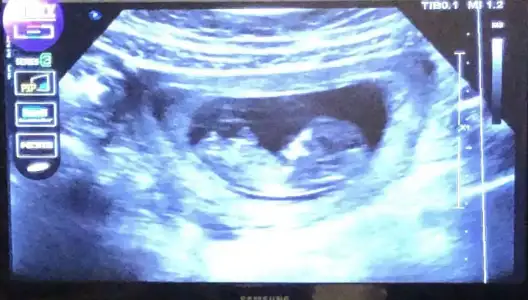

Kızlar dün attım ama kimse yorum yapmadı 🥺 nub teorisine göre sizce cinsiyet ne? Doktor birşey söylemedi

Eklentiler

• 6855C3AF-A877-47FE-B6B9-1E8B31A0FE74.webp

6855C3AF-A877-47FE-B6B9-1E8B31A0FE74.webp

30,8 KB · Görüntüleme: 69